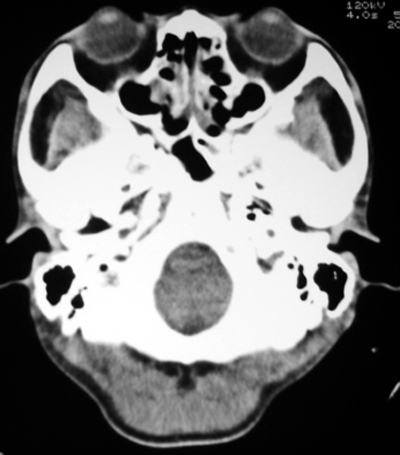

以下是引用bmw011在2009-4-23 13:23:00的发言:[br]考虑鼻息肉,上颌窦、筛窦炎

以下是引用syfszcw在2009-4-23 13:21:00的发言:[br]双侧上颌窦 筛窦慢性炎症,鼻息肉 会厌ca[br][br][本贴已被 syfszcw 于 2009-4-23 13:36:46 修改过]

以下是引用随光逐影在2009-4-23 19:35:00的发言:[br]1)鼻咽、口咽、左侧鼻腔及右侧鼻后孔处新生物,考虑息肉可能性大。2)双侧上颌窦及双侧筛窦炎症,不排除双侧上颌窦内息肉可能。